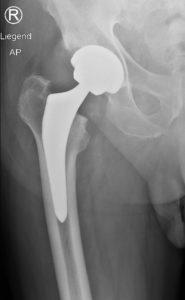

Operative Therapie

Wenn die Schmerzen durch eine konservative Therapie nicht mehr behandelt werden können und, die Lebensqualität sinkt, ist ein operatives Verfahren möglich. Hierzu gibt es künstliche Gelenke mit denen die geschädigten Gelenkoberflächen ersetzt werdem, die sogenannten Hüftendoprothesen. Nach exakter Planung, anhand von Röntgen- und ggf. auch MRI-Bildern, erfolgt die Festlegung des individuellen Modells und die Größe der neuen Gelenkpartner. Wenn immer möglich benutzen wir einen gewebeschonenden, minimalinvasiven Zugangsweg zum Hüftgelenk. Entgegen den früher durchgeführten Schnitten durchtrennen wir weder Muskeln noch lösen wir diese vom Knochen ab. Nach Einpassen der vorher geplanten und während der Operation kontrollierten neuen Gelenkpartner, werden diese meist zementfrei im Knochen verankert. Die Fixation wird je nach Knochenqualität, Alter und Prothesentyp gewählt. Daraus ergibt sich ein sehr geringes Gewebetrauma und es kann gewährleistet werden, dass bei jeder Operation die bestehende Anatomie berücksichtigt und eine optimale Funktion wiederhergestellt wird.

Nachbehandlung

Im Allgemeinen ist die Hüftprothesenversorgung ein Standardeingriff. Eine Vollbelastung ist mit unserem gewebeschonenden Eingriff sofort nach der Operation möglich. Es werden ausreichend Schmerzmittel in das Gewebe einbracht, unterstützt von Tabletten und eventuell Infusionen. Schon am ersten Tag werden die ersten Steh- und Gehversuche an zwei Gehstöcken absolviert. Hier hilft Ihnen die Physiotherapie. Diese aktive Mobilisation wird über die folgenden Tage des Aufenthaltes zunehmend erweitert, bis eine Gehstrecke und Treppenstufen gut bewältigt werden können . Die Benutzung der Gehstöcke wird für die nächsten 4 Wochen empfohlen, um ein harmonisches Gangbild zu erhalten, aber auch um die operierte Hüfte zu entlasten. Ob im Anschluss an den Spitalaufenthalt eine ambulante Physiotherapie oder ein Aufenthalt in einer Rehabilitationsklinik nötig ist, kann im Team mit Patient, Arzt und Physiotherapeut entschieden werden. Somit sollte nach einer Dauer von 8 bis 12 Wochen ein schmerzfreies und normales Gangbild, ohne Unterarmgehstützen, wieder möglich sein.